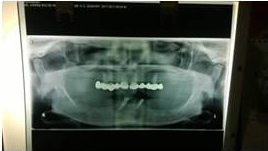

X-ray of Implant

Single Tooth Implant